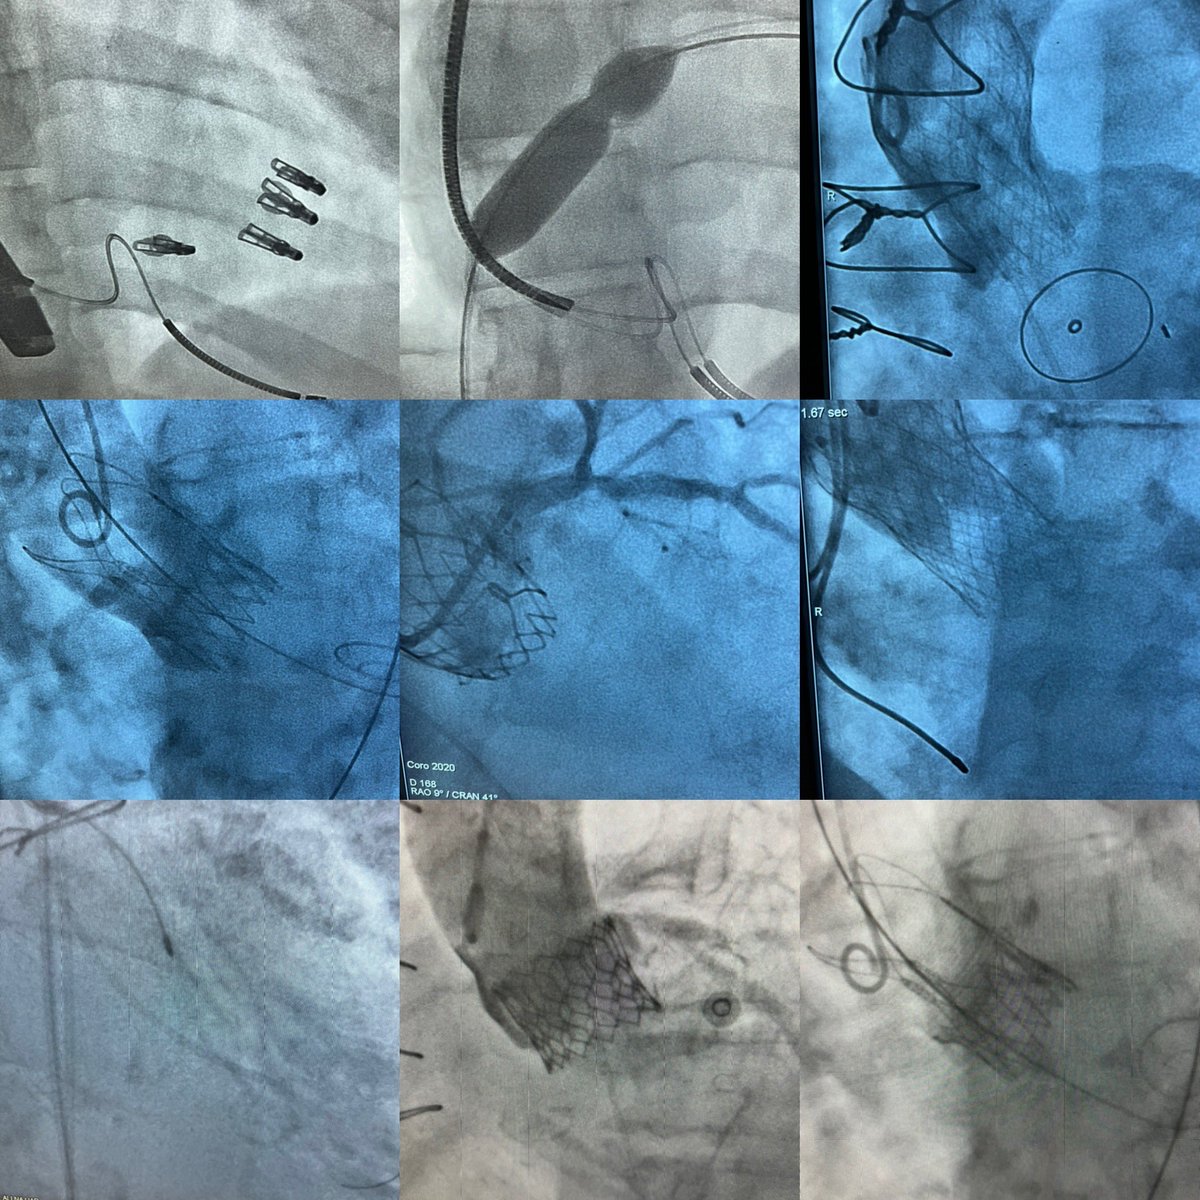

From the CABANA trial: Patients with #HFpEF benefited even more from #Afib ablation regarding:

🔸Death/CV 🏥

🔸AF recurrence

Despite the greater benefit for HFpEF pts, their risk of recurrence remained ⬆️ than in those w/out HFpEF

📎: jacc.org/doi/10.1016/j.… #JACCHF